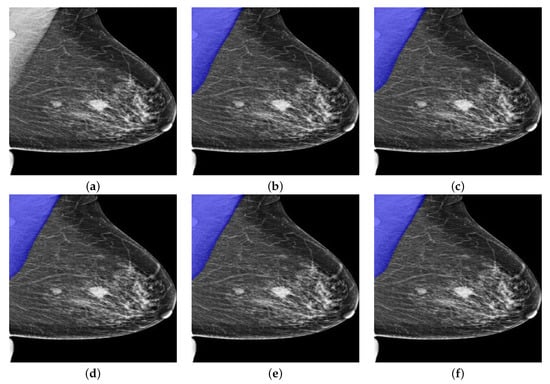

As can be seen in Table 3, all Deeplabv3+ models showed over 95% of IoU, 99% of GPA, 95% of Sensitivity and Specificity, which validated the effectiveness of deeplabv3+ model for pectoral segmentation task. However, the overall DSC and Jaccard metrics remained to be low as the averaged DSC is just around 95% while the averaged Jaccard is only around 90%. Nevertheless, the model based on InceptionResNetv2 consistently showed high performance in terms of IoU, GPA, DSC, Jaccard and Specificity though the Sensitivity is slightly lower than other models. As can be seen from Table 4, the Deeplabv3+ model that takes InceptionResNetv2 as backbone showed predominating performance due to the depth of InceptionResNetv2 and the number of the training parameters. Interestingly, the Deeplabv3+ model that takes MobileNetv2 as the backbone showed much higher performance than UNet. This finding further boosted our choice on using Deeplabv3+ as the basic framework. One segmentation example from OPTIMAM by Deeplabv3+ with different backbones is given in Figure 10. The blue areas in the figures indicate the segmentation results given by the segmentation models.

As can be seen from Figure 10a, there are two masses in the breast region while there is one more mass-like artefact in the pectoral muscle. In this scenario, pectoral segmentation plays a key role in removing the artefact, which turns out the be the side benefit of pectoral removal. The segmentation results seem to quite similar while the MobileNetv2-based model seems to give the best results as it consistently provides highest IoU, GPA, DSC and Sensitivity. Another segmentation example from INbreast dataset by Deeplabv3+ with different backbones is shown in Figure 11.

Figure 10. A segmentation example from OPTIMAM by Deeplabv3+ with different backbones. (a) Pre-processed image. (b) D L R e s N e t 18 : 98.29% of IoU, 99.73% of GPA, 97.70% of DSC, 95.50% of Jaccard, 99.89% of Sensitivity, and 99.72% of Specificity. (c) D L R e s N e t 50 : 99.18% of IoU, 99.87% of GPA, 98.35% of DSC, 96.75% of Jaccard, 99.90% of Sensitivity, and 99.87% of Specificity. (d) D L M o b i l e N e t v 2 : 99.35% of IoU, 99.90% of GPA, 98.64% of DSC, 97.32% of Jaccard, 100% of Sensitivity, and 99.89% of Specificity. (e) D L X c e p t i o n N e t : 98.87% of IoU, 99.83% of GPA, 98.08% of DSC, 96.23% of Jaccard, 98.04% of Sensitivity, and 99.99% of Specificity. (f) D L I n c e p t i o n R e s N e t v 2 : 98.99% of IoU, 99.85% of GPA, 98.30% of DSC, 96.65% of Jaccard, 98.15% of Sensitivity, and 100% of Specificity.